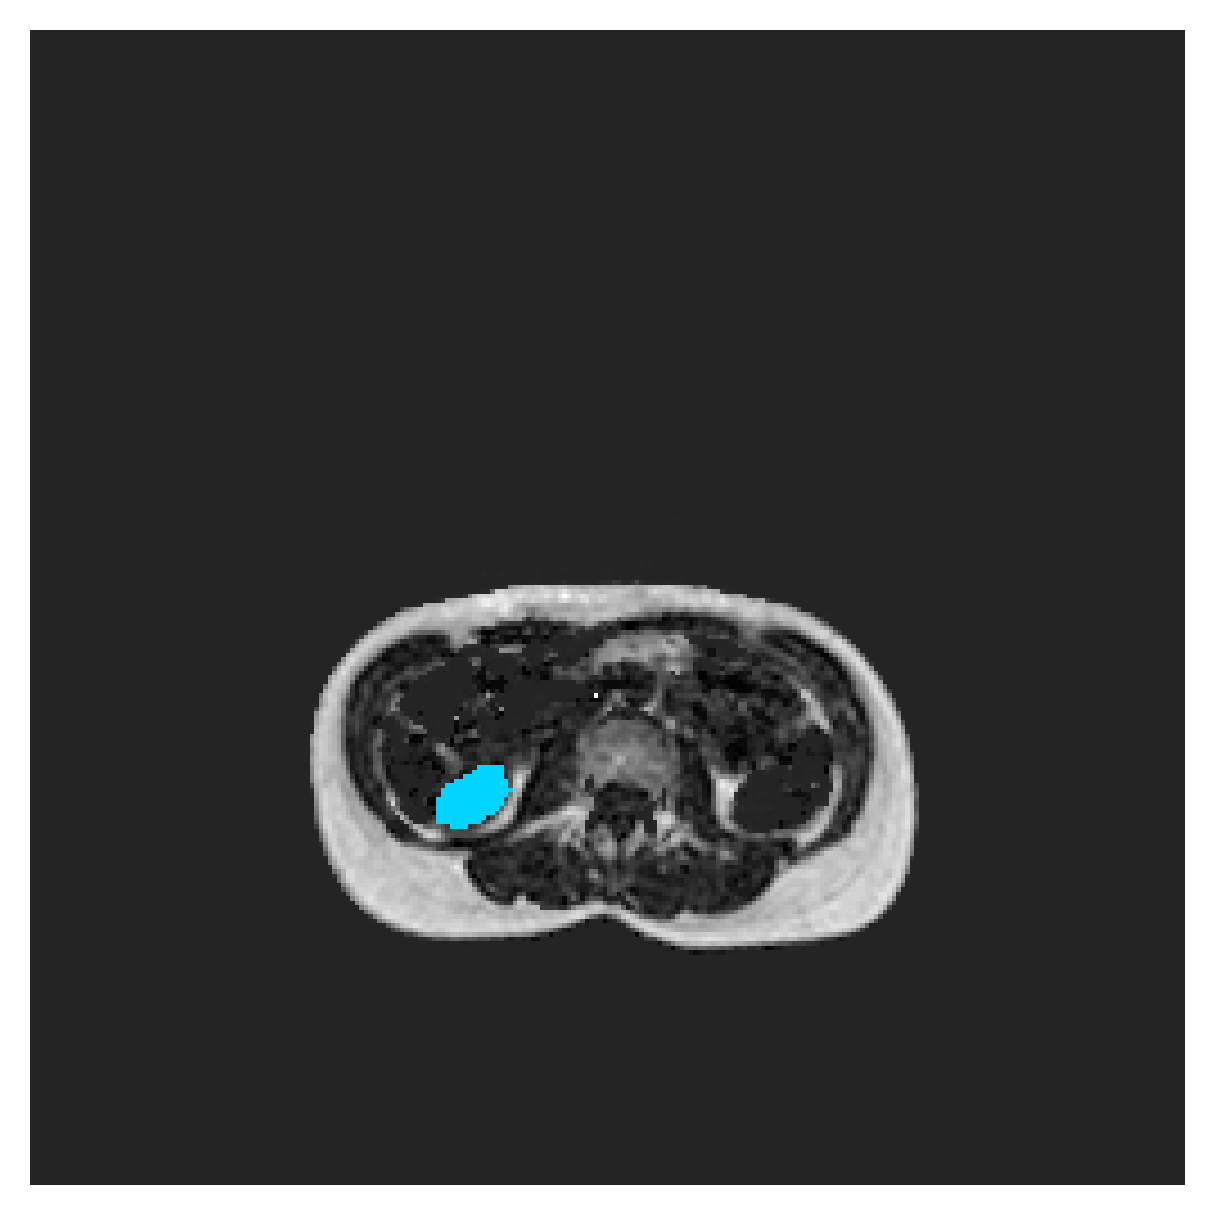

We normalize the volumes and resize the slices to pixels. As the official dataset comes with full annotations, we create a synthetic point ground truth. This is done by first randomly choosing the centers of the point annotations within the class masks, followed by filling an ellipse with axes lengths of and (in pixels) around each center. The intersections of these elliptic discs with the underlying full annotations are then used as our point ground truth. See Figure 2 for an example of the created weak annotation mask. The point annotations are created for every slice, one for each foreground object present in the slice.

The images contain two channels, one for water and one for fat content. For training, we normalize the volumes (per channel) and use 2D slices in the coronal plane, sized . The weak annotations are created synthetically, following the same procedure as described for the ACDC dataset.

For ACDC, we compute the maps on 2D slices. In the case of POEM, however, the majority of 2D slices contain only background, and even those slices that contain foreground never contain all of the classes. As a lack of a class in an image results in a zero distance map (by implementation design), that particular class can be arbitrarily segmented without an increase in the loss. To circumvent this issue, we use a simple map of ones for every absent class, assuring some minimal amount of penalty. In addition, considering that the POEM data is highly anisotropic and its coronal slices may contain unconnected regions belonging to the same class, we run a separate set of experiments with distance maps calculated in 3D volumes, using all slice-wise point annotations. In 3D, since all classes are present in every volume, the problem of zero distance maps and no supervision is avoided entirely.